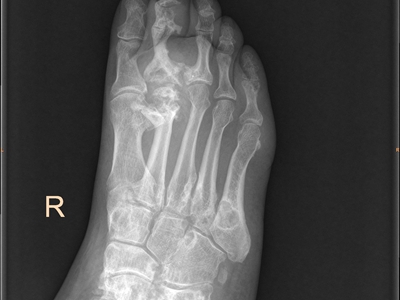

痛风是由于嘌呤代谢紊乱和尿酸排出减少,而引起的尿酸盐结晶沉积性病变,可累及指关节、第一跖趾关节、耳廓等处,造成急性炎症反应性滑膜炎。常于中老年发病,男性发病率明显高于女性,以皮下出现痛风石、痛风性关节炎、关节畸形、肾结石或肾脏病变为临床特征。痛风治疗原则为治疗高尿酸血症和控制关节炎。

痛风病程较长,常反复发作而迁延不愈形成痛风石,是痛风的特征性临床表现,常见于指关节、第一跖趾关节、耳廓等处。外观为隆起、大小不一的不规则的黄白色赘生物,表面菲薄,破溃后排出白色粉状或糊状尿酸盐结晶物,经久不愈,但较少继发感染。部分患者伴有肾结石及肾脏病变。